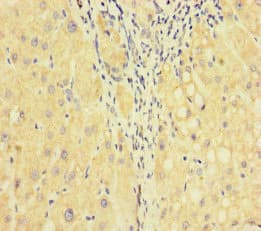

Anti-Factor V antibody(ab234849)

Rabbit Polyclonal Factor V antibody. Suitable for IHC-P, ICC/IF and reacts with Human samples. Cited in 1 publication. Immunogen corresponding to Recombinant Fragment Protein within Human F5 aa 1450-1650.

Applications ICC/IF, IHC-P